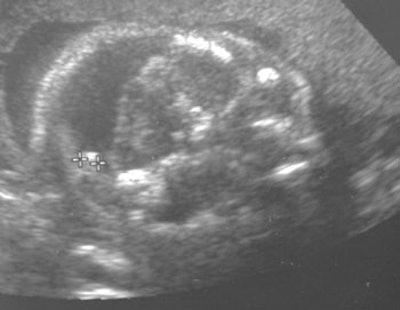

Segundo, un exceso de material quirúrgico y tejido adiposo a menudo perturban las ondas sonoras. Éste fue el caso de una paciente de Mount Sinai. La ecografía de una mujer morbosamente obesa, que también había sido sometida a la colocación de una malla abdominal para reparar una hernia, sugería que su feto podía tener encefalocele, una afección en la que hay un espacio en el cráneo. Pero la imagen no era conclusiva.

![]() |

"Las ondas sonoras no podían penetrar la pared abdominal de la paciente obesa," dijo Saphier. "Pero la RM resultó ser bastante útil. Confirmó la anomalía sospechada y el embarazo fue interrumpido."